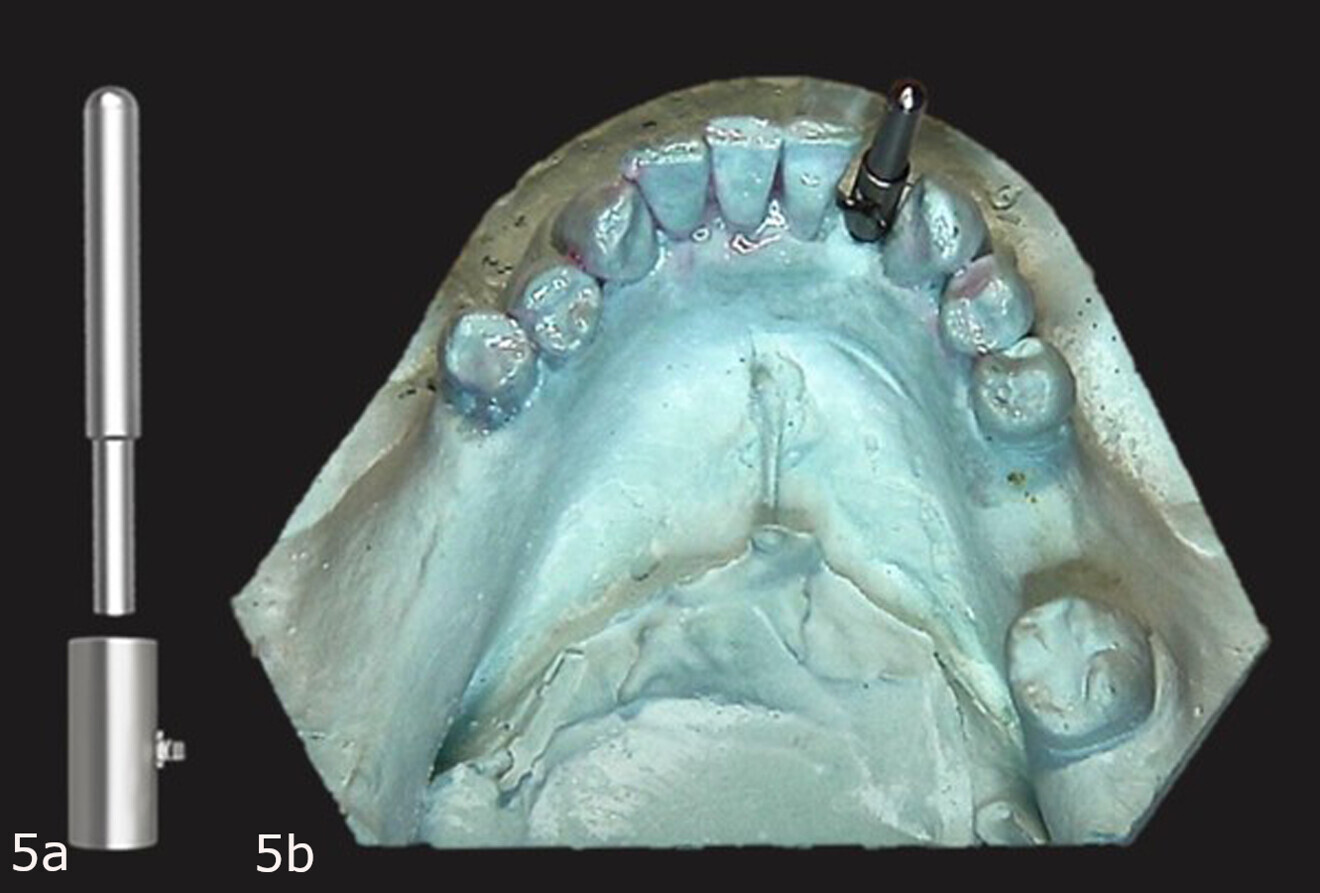

Figs. 5a & b: Guide Right guide sleeve and post (a). Guide sleeve placed over the guide post with the retentive cleat positioned on the lingual aspect (b).